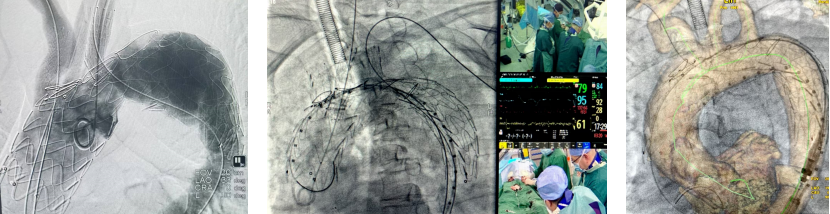

★ 病例1

73岁男性,主动脉夹层合并壁间血肿,心肺功能差,无法耐受开放手术。

手术关键步骤:

脑保护:经双侧锁骨下动脉置入8F长鞘至降主动脉,制造临时Ⅰ型内漏,再通过双供管连接颈动脉与肱动脉鞘管,建立转流通道,确保支架释放过程中脑部持续灌注。

支架定位与开窗:使用TAG CADS支架,释放至80%时造影调整位置,避免遮挡冠脉开口。

随后经左颈动脉穿刺,使用NPAS肝穿针原位开窗,逐级扩张后植入Viabahn支架。

右颈总动脉:相同操作,植入VBX支架,重建无名动脉系统。

远端覆盖:股动脉入路植入cTAG支架,与近端支架重叠,确保降主动脉以远血供。

锁骨下动脉二期重建。

(二)ZIPPER支架系统

团队在全球范围内率先完成6例ZIPPER支架植入,其中前三例均为该中心开展。

Zhang Invented Percutaneous Permanent Endovascular Repair;

图:前三例

植入仅需对准左颈总动脉,导丝进入无名动脉后即可释放;

手术时间从初期的2小时40分钟缩短至42分钟,流程大幅简化。